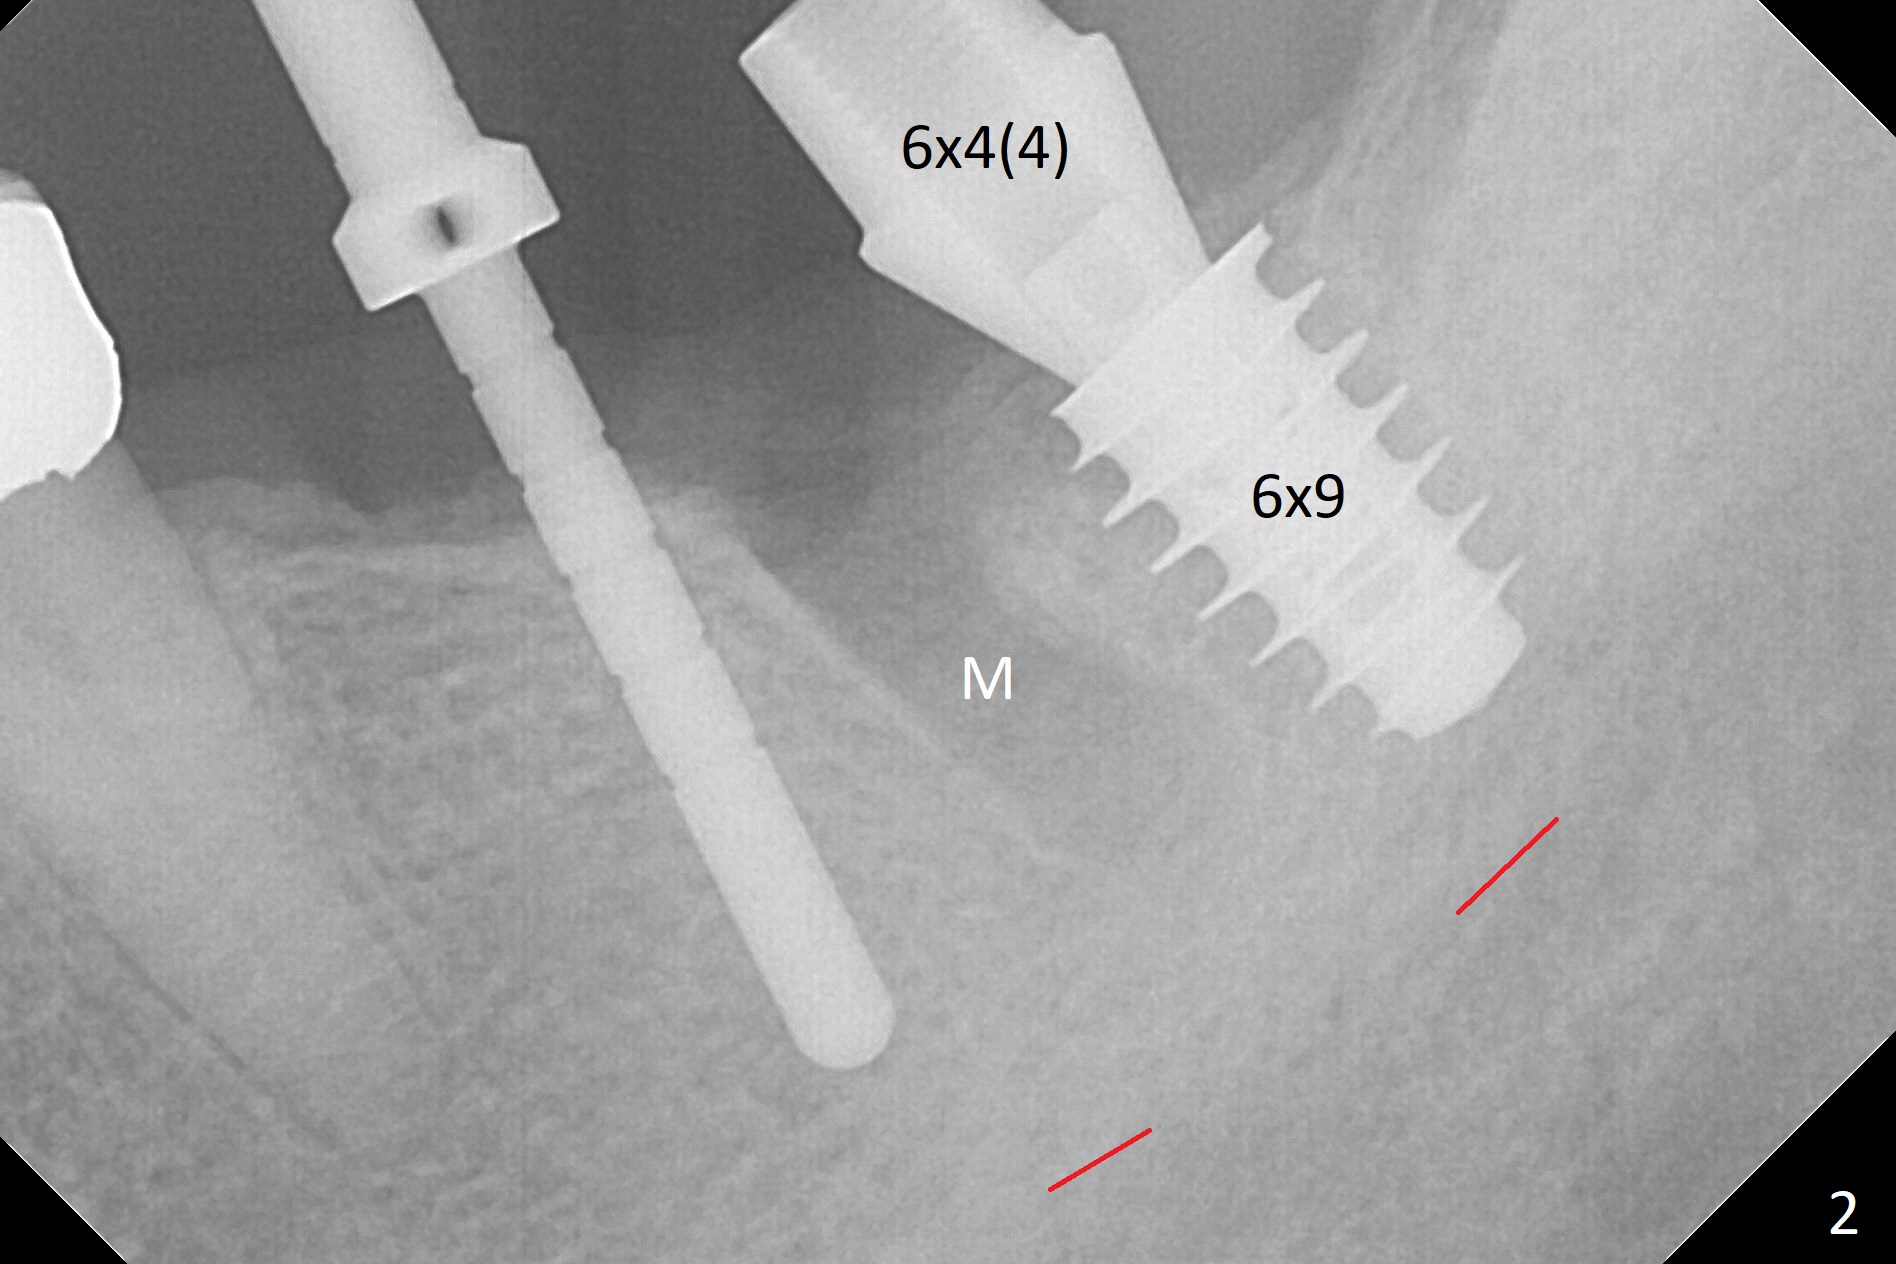

After extraction of the residual root at #18 (Fig.1), the septum is narrow, while the distal socket seems to be the most appropriate site for implant placement (Fig.2 (M: mesial)). In fact the implant needs to tilt slightly distally (relative to the original trajectory of the distal socket, Fig.3 green) to occlude with the opposing tooth. The implant at #19 could be placed more mesially (Fig.4 (*: Vera Graft)).